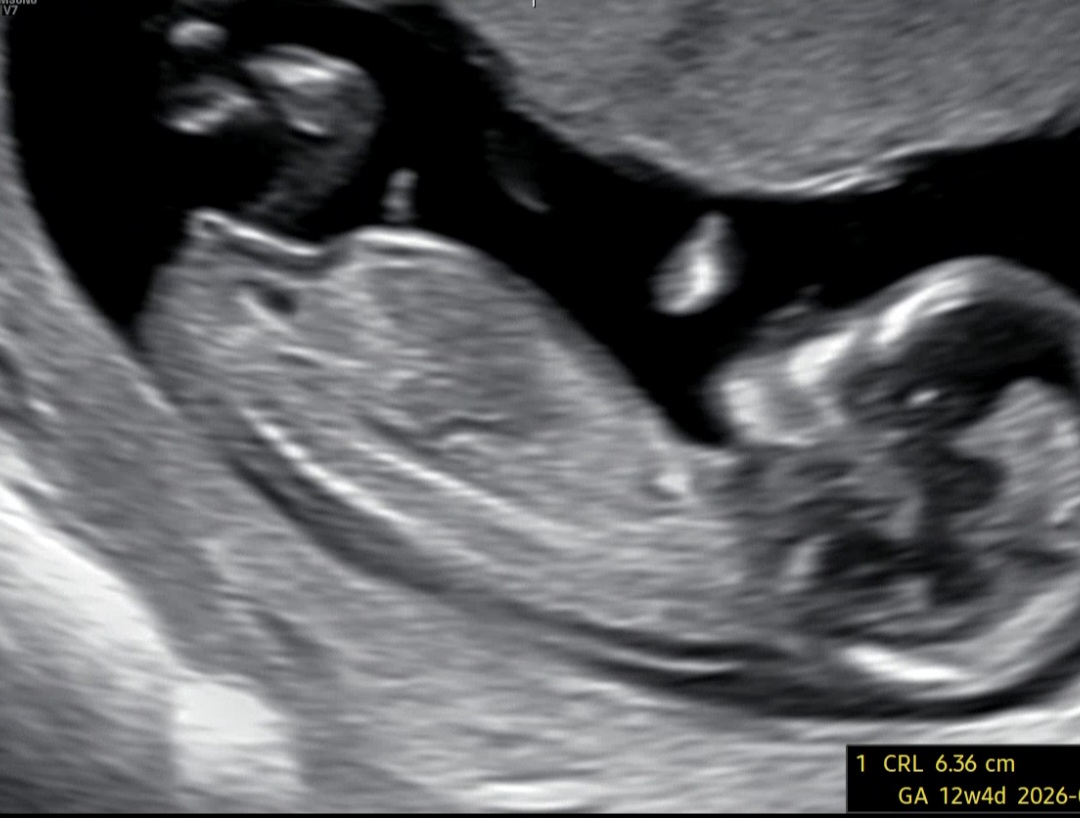

오늘 12주4일차 초음파입니다. 각도법 찾아봤는데 어디를 기준으로 잡고 각도를 재야하는지 어렵네요ㅠㅠ 고수님들 투표 부탁드립니다~